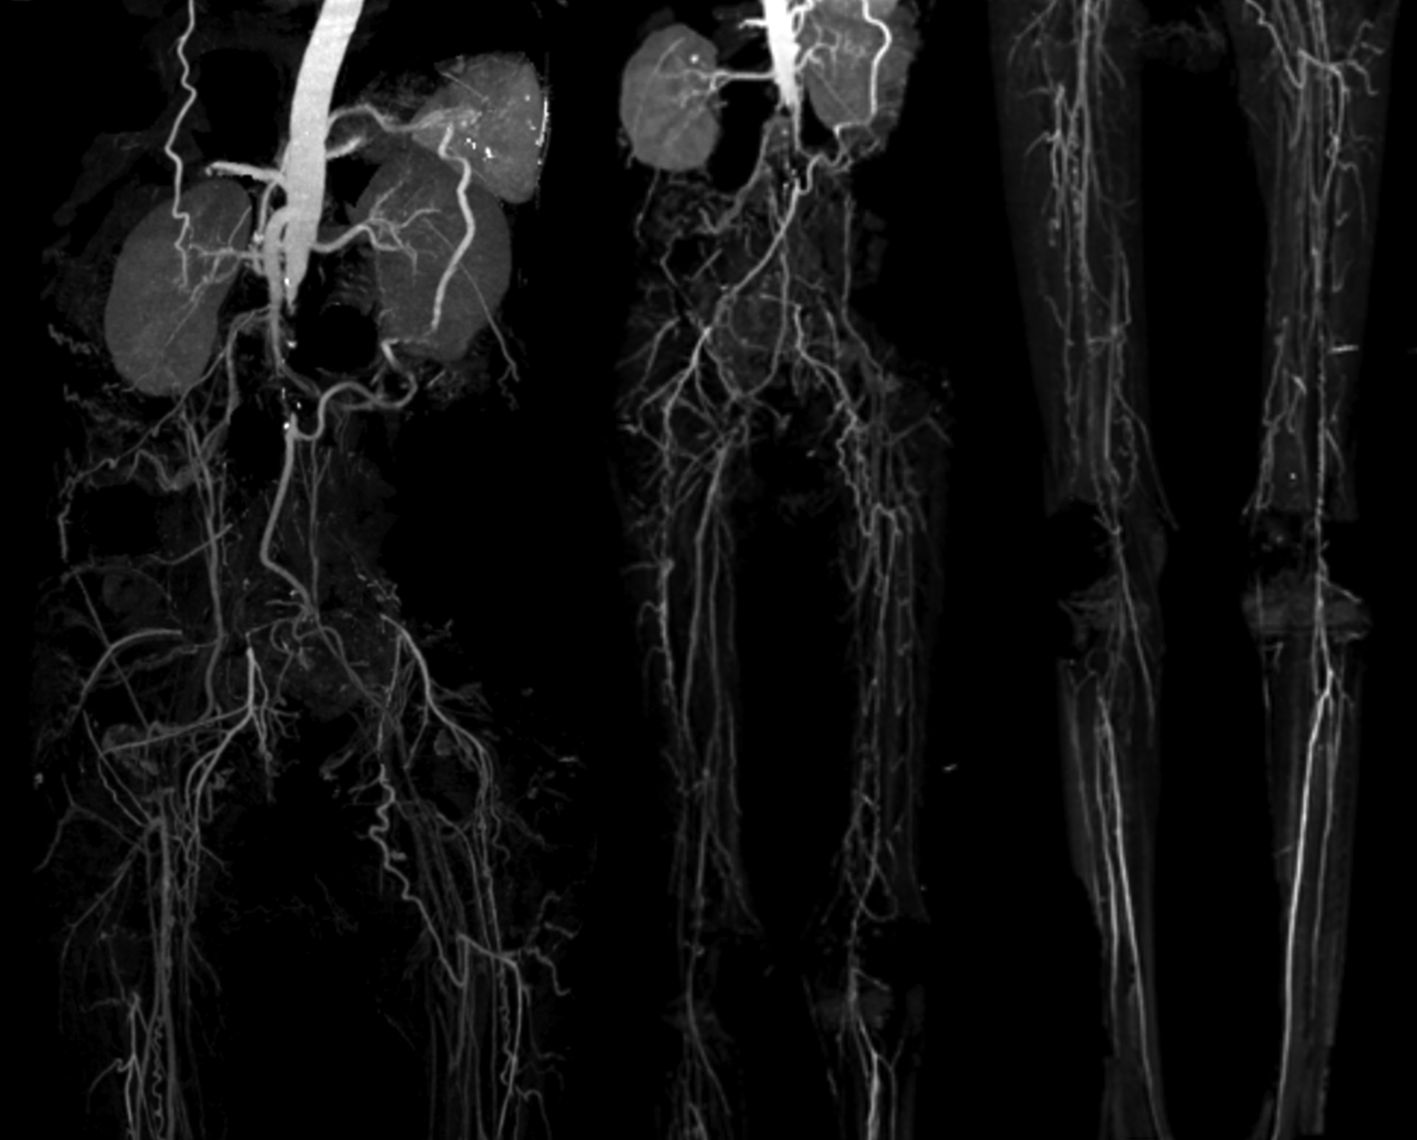

His vital signs were within normal limits. Physical examination showed cold extremities, non-palpable bilateral dorsalis pedis artery pulsation, and gangrene on left toe (Figure 3A). Significant laboratory examination results were erythrocyte sedimentation rate of 99 mm/hour, D-dimer of 3250 ng/mL, fibrinogen of 734 mg/dL, albumin of 0.8 g/dL, total cholesterol of 347 g/dL, LDL of 257 g/dL, HDL of 54 g/dL, triglyceride of 278 g/dL, +3 urinary protein with 24-hour urinary protein of 19840 mg/24 hour. Left ankle brachial index (ABI) of the patient was 0.25 and right was 0.33. Lower extremity duplex ultrasound (DUS) was consistent with lower extremity CT-Scan Angiography (CTA) revealed occlusion with thrombus in abdominal aorta starting from 2 cm below renal artery until bilateral superficial femoral artery (SFA), distal flow filled from collateral from branch of coeliac trunk and branch of superior mesenteric artery (Figure 4).

Occlusion with thrombus in abdominal aorta starting from 2 cm below renal artery until bilateral superficial femoral artery, distal flow filled from collateral from branch of coeliac trunk and branch of superior mesenteric artery.